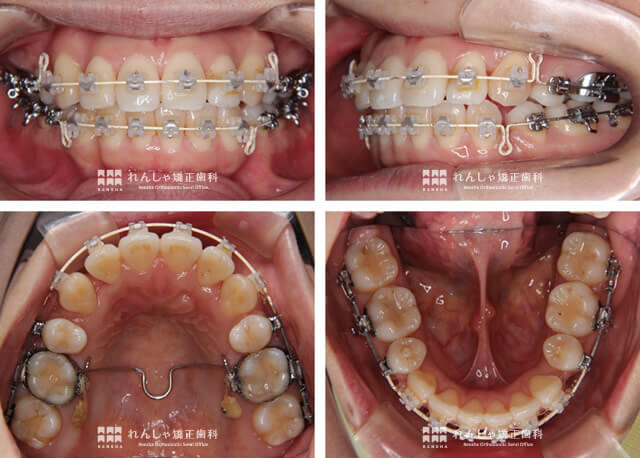

治療経過②

治療の初期は非常に細く柔らかいワイヤーを使用する(形状記憶)

矯正治療の初期は、皆さんが想像されるよりも細いワイヤーを使った装置を使います。このワイヤーは、形状記憶機能を持つ柔らかいもの。しかしたとえそうであっても、治療の初期はかなり痛みを伴います。

青矢印

この時期はまだ、がたつきが大きい状態です。歯の表面に装置を装着すると、当然唇に装置がぶつかってしまい、口内炎になりやすい。とくに治療初期は慣れてもいないので、口内炎が頻発することも。ワックスでカバーしてもらうこともありますが、食事の際などに外れやすいため、よく当たる箇所にはこちらで樹脂製のカバーを施すこともあります。

黄色矢印

がたつきは、基本的に前歯に集中しがちです。重度のがたつきがあると、抜歯をしてもスペースがギリギリになる場合も少なくありません。また前歯のがたつきを解消している間に、奥歯が前方に移動してしまい、がたつきの解消が難しくなってしまうこともあります。

とくに上奥歯が前に移動してしまうと、出っ歯になってしまうので上奥歯の後方維持が重要になります。E.Kさまのケースでは、上奥歯を維持するために歯科矯正用アンカースクリューというネジを併用して対応しました。